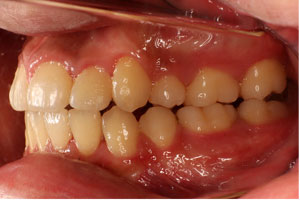

こちらの初診(男性)の患者さんは、開咬合 / 叢生歯列の症状がありました。

1期治療 8歳9ヶ月 2期治療 12歳4ヶ月から治療を開始し、1期治療 7ヶ月 2期治療 2年5ヶ月の間、スタンダードエッジワイズ法(与五沢エッジワイズシステム)を用い矯正治療を行いました。

| 症例分類 | 開咬合 / 叢生歯列 / 偏位咬合 | |||||||||||||||||||||||||||||||||||||||||||||||||||||||||||

| 12歳4ヶ月 | 15歳8ヶ月 | |